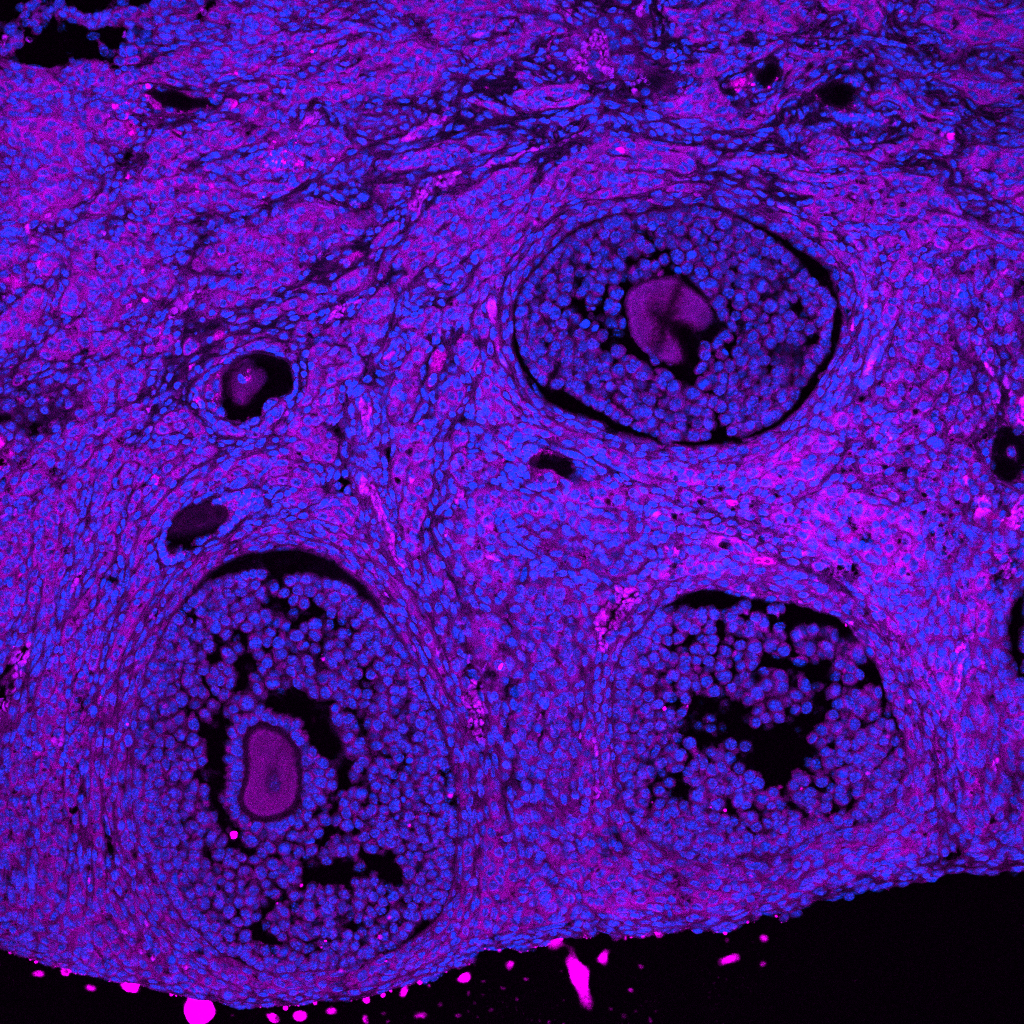

Imaged by Ruijuan Xu

Currently a PhD student at King’s College London, Ruijuan focuses on several key research areas in her project. These include the characterization of AI-generated small molecule compouns as novel FSHR inhibitors, the molecular characterization and analysis of how FSH glycosylation variants modulate cAMP production, FSHR oligomerisation, and FSHR trafficking. Before joining King’s College London, Ruijuan earned her degrees in Clinical Medicine in China and worked as an OB/GYN.

Milan is a second year PhD student studying ovarian ageing. She is interested in investigating the stiffness and material properties of the organ across a wide range of ages using biophysics, proteomics and biochemistry. Previously, she completed her undergraduate in Chemistry with Biomedicine and her Master’s year in single-molecule Biophysics.